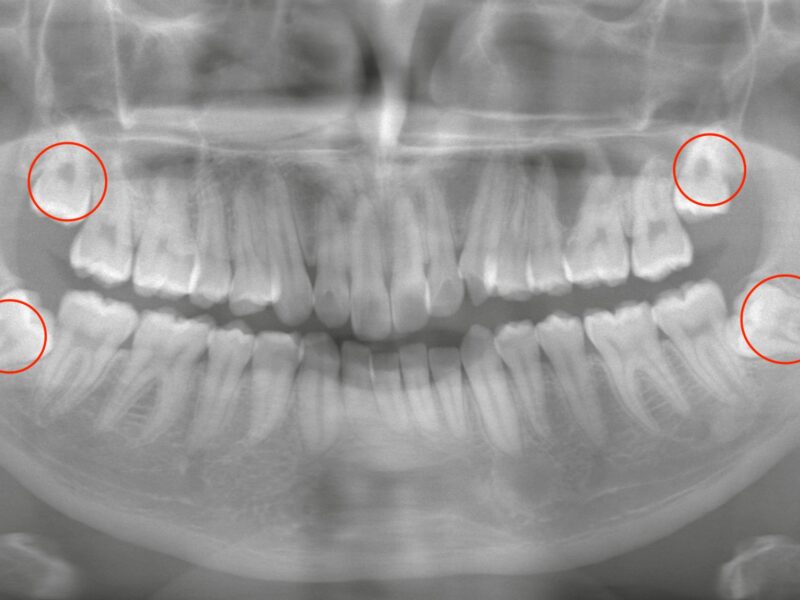

特徴4高精度診断を可能にする「歯科用CT」 -